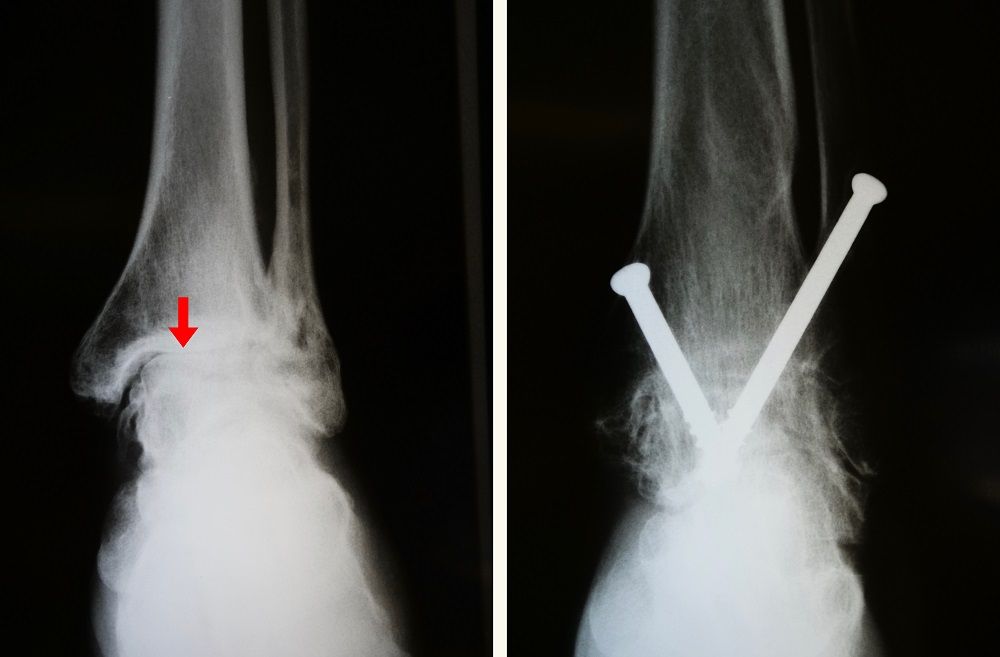

Arthritis Of The Foot And Ankle Orthoinfo Aaos